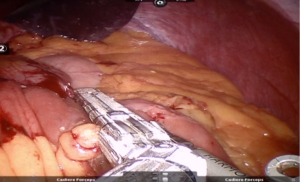

Window created in Jejunum mesentery just proximal to Gastro-jejunostomy (towards left side) and jejunum transacted using white/tan-60 mm cartridge thus creating a biliopancreatic limb of 100 cm (Figure 13).

Jejuno-jejunostomy (side to side) is made using blue/tan 60 mm cartridge) (Figures 14,15).